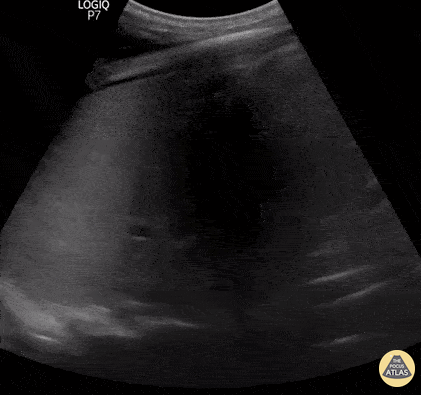

Lignes B pathologiques. Ce GIF montre la présence de nombreuses lignes B (plus de 3 par espace intercostal). Ces artéfacts verticaux, "en queue de comète", partent de la ligne pleurale et s'étendent jusqu'au bas de l'écran sans s'atténuer, effaçant les lignes A. Ils signent une perte d'aération pulmonaire

Présence d’au moins trois lignes B par espace intercostal, s’étendant jusqu’au fond de l’écran, effaçant les lignes A et se déplaçant avec le glissement pleural.

- Syndrome interstitiel (lignes B) → excès de liquide ou épaississement interstitiel.